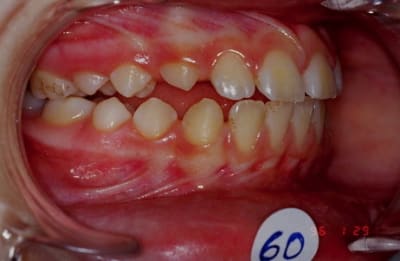

Voila à la demande de bjc et pour que ma reponse soit constructive je présente une méthode simple et fiable pour faire le diagnostic différentiel entre les vraies et les fausses supraclusions valables surtout chez des sujets jeunes de moins de 14-15 ans. Chez des adultes il faut voir autre chose pour évaluer la perte de DV articulaire.

1- Marche d'escalier entre les bords libres des incisives et les secteurs latéraux à chercher. Si la marche est au niveau max il s'agit de vrai supra, si la marche est à l'arcade inf il s'agit plutôt d'infra.

2- Dans le cas de fusse supra l'espace libre intermolaire est plus importante et la hauteur des couronnes cliniques des dents latérales inférieures est réduite

3- Chercher l'interposition linguale latérale car c'est l'origine du problème

D'une part j'ai dit evaluer la courbe de Spee ce qui veut dire tout simplement evaluer son impmoyenne ou trop plate. Ceci sera completer par l'etude de la position du borb libre de l'incisive inf par rapport au plan occlusal de Ricketts, passant par les surfaces occlusales de 6, 5 et 4 et sans regarder les bords libres des incisives comme celui utilise dans la plupart de technique d'arc droit. Une chose est sure des le moment qu'on utilise un arc continu pour finir nos traitement la courbe de Spee est diminuee pour ne pas dire aplati, et l'occlusion de fin de traitement actif n'est la meme de fin de contention n'est la meme en post contention. L'occlusion va s'assoir et s'adapter aux demandes physiologiques, fonctionnelles et anatomiques de chaque cas, a condition que nos fins de traitement repondent a certains criteres de qualite fonctionnelle, occlusale, articulaire et esthetique.

Quant a evaluer le siege du probleme supra vraie ou infra, il faut que cela soit fait avant la recuperation de classe I, car l'ordre chronologique du deverrouillage dentaire est transversal d'abord, vertical ensuite et sagittal enfin. Donc on est oblige de decider assez tot d'ou vient le probleme pour prendre les moyens therapeutiques necessaires en fonction de cela. Je donne un exemple: si le cas presente une typologie defavorable avec une supra vraie et je place un arc continu seul qui va ingresser mes incisives, mais il va egresser les secteurs lateraux je risque d'aggraver ma typologie vertical. L'usage d'un arc de base d'ingression doit etre decide des le debut pour ingresser les incisives sans provoquer l'egression des dents laterales. Par contre il est vrai que mon evaluation du probleme doit etre permanente tout au long du cas et en cas d'erreure il n'y a que les imbeciles qui ne change pas d'avis.Pour repondre a la proposition de bjc, en realite je ne vois pas comment le montage pourrait nous aider a faire le diagnostic differentiel, j'attends qu'on m'explique!?